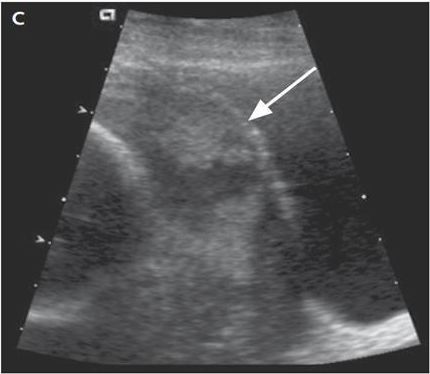

△

箭头指的不规则的无回声区是胎盘组织。